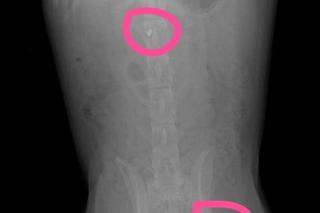

Wolontariusze wrocławskiej organizacji Ekostraż zaapelowali o wsparcie dla suczki Kevli, którą ktoś postrzelił z wiatrówki w Gruzji. Śrut utknął w kręgosłupie i doprowadził do paraliżu. Kevla nie może chodzić, w Gruzji nie miała szansy ani na odpowiedni dom, ani nawet na diagnostykę.

Niestety, pewne jest, że Kevla nie będzie nigdy chodzić, bo śrut i przemieszczony odłamek utkwił w rdzeniu kręgowym. Będzie mogła się poruszać tylko na wózku. Problemem jest także odleżyna, którą trzeba myć i smarować. Wolontariusze walczą z nią od tygodni, a ona wciąż otwiera się, jątrzy i sprawia suczce ból. Ponadto u Kevli wykryto dwie bakterie w pęcherzu. Zaczęto leczenie, które jest wymagające i długie.